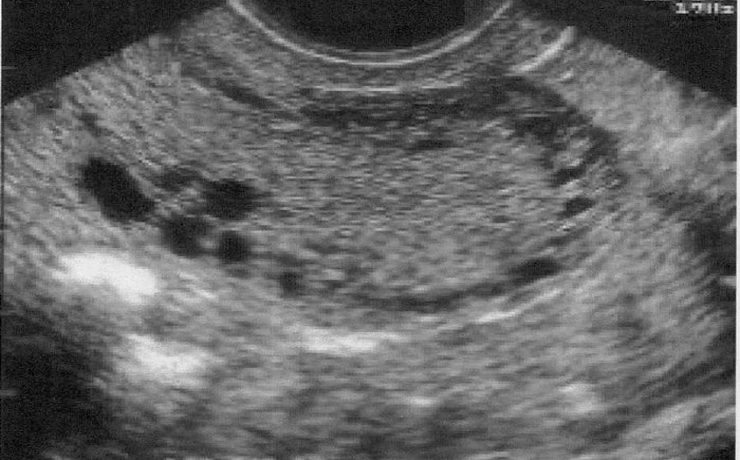

Fibroadenoma de tejido mamario ectópico axilar

Es el tumor benigno más común de la glándula mamaria de mujeres jóvenes. A pesar de que un 95% de las mujeres existe tejido mamario en la axila (cola de mama) y de que incluso en 6 de cada 100 es clínicamente evidente. Los reportes de este tumor en la